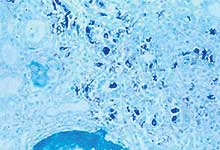

"Hybridation in situ" pour la détection de génome du PCV2 dans le rein d'un porc atteint de SDN. Les cellules colorées en bleu correspondent principalement à des macrophages, qui contiennent de l'acide nucléique de PCV2.